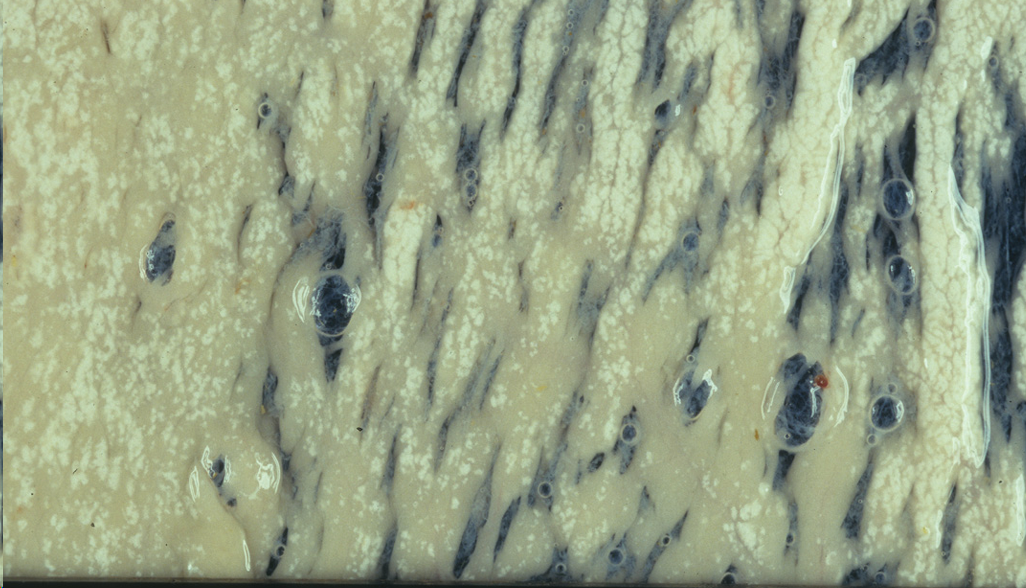

Hialinosis muscular o enfermedad del musculo blanco

Mas información: IMPORTANTE, ESTA CAE. Hialinosis muscular o enfermedad del musculo blanco, carne palida o cocida. Se puede dar en el cardiaco o en el estriado.